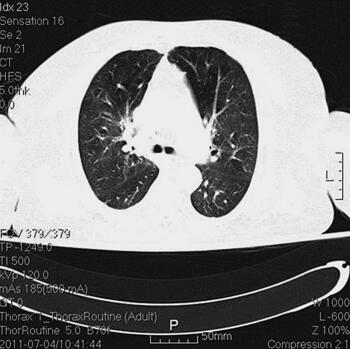

诊治经过:入院后留置右锁骨下深静脉导管,监测CVP。患者血压逐渐平稳,停用多巴胺。继续机械通气,头孢哌酮-舒巴坦钠针剂及阿奇霉素针剂联合抗感染,甲泼尼龙及多索茶碱解痉平喘,改善微循环,化痰等对症支持治疗。并予肠内营养,胰岛素微泵控制血糖。复查胸部CT(7月4日)(图2),感染较前明显吸收;复查(7月4日)CRP 10mg/L,PCT 0.22ng/ml。

图2 胸部CT(7月4日),感染较前明显吸收